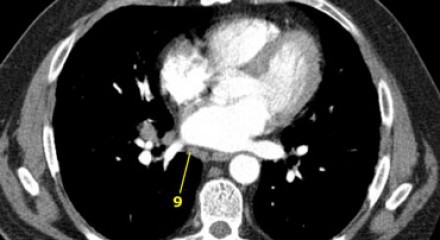

9. Linfonodos do ligamento Pulmonar

Linfonodos do ligamento pulmonar estão dentro do ligamento pulmonar, incluindo aqueles na parede posterior e inferior da veia pulmonar inferior.

O ligamento pulmonar é a extensão inferior das reflexões da pleura mediastinal que cercam o hilos.